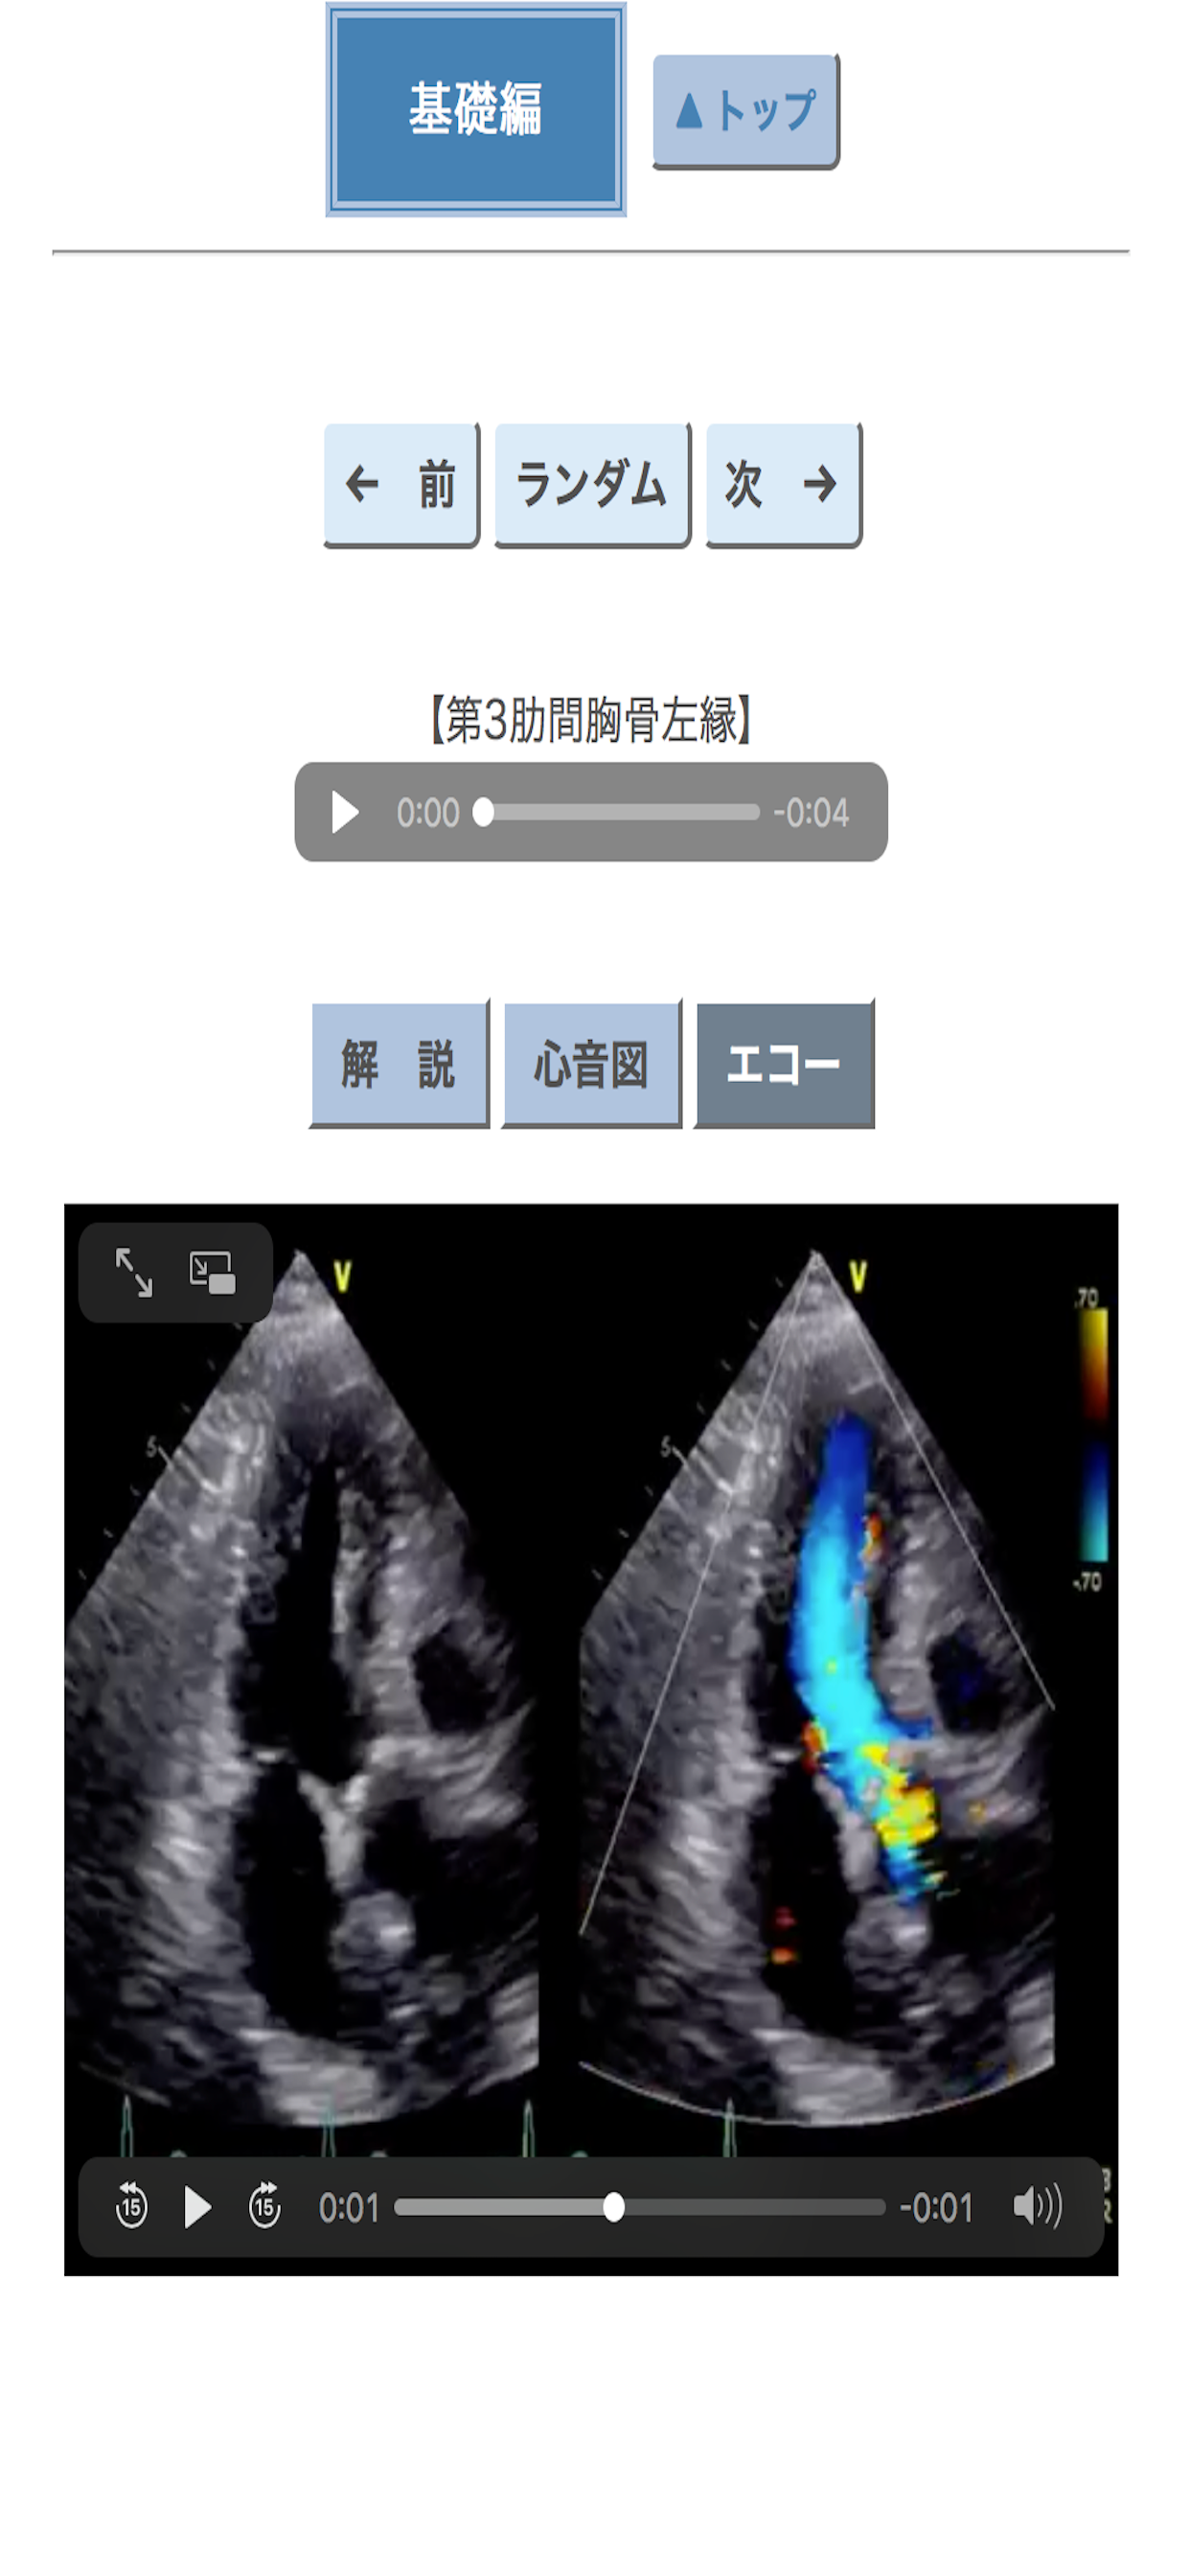

心臓はおしゃべりです.喜び,憂い,興奮,冷静,快さ,喘ぎ,充実,不満・・・いつも1人で何かを呟いています.うまく聞き取れないことも少なくありませんが,聴診器を胸に当てる前はいつも気持ちが高ぶります. この心臓語が持つ面白さを伝えるために本アプリ「ポケット心音」を作成しました.聴診器の歴史や心音のトリビアも紹介しています.心臓の聴診に興味を持つきっかけになればこれ以上の喜びはありません.